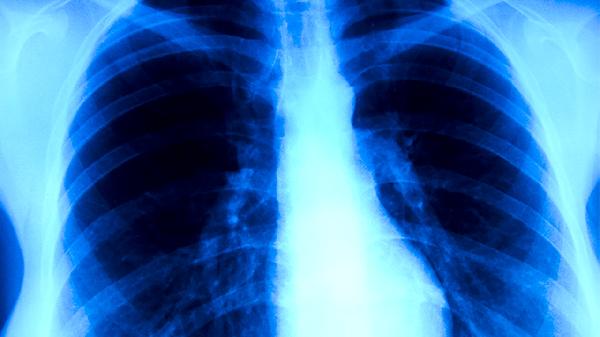

慢性肺源性心脏病急性发作的治疗方法主要有氧疗、药物治疗、机械通气、控制感染、纠正心力衰竭等。慢性肺源性心脏病急性发作通常由呼吸道感染、肺动脉高压加重等因素诱发,表现为呼吸困难加重、下肢水肿等症状。